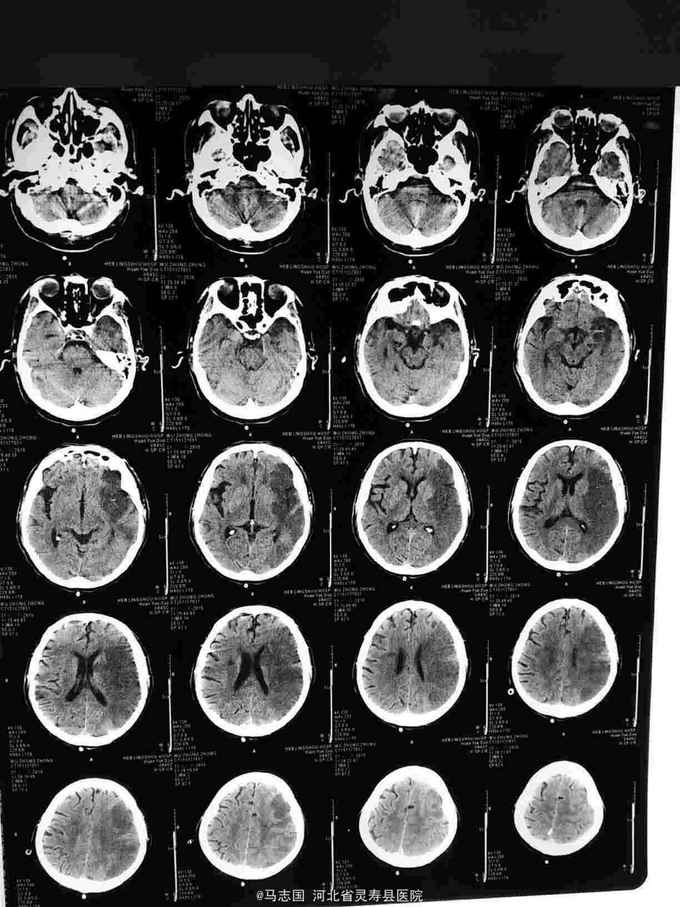

被发现意识不清2小时入院。病例特点1.老年男性2.既往”慢性阻塞性肺疾病,肺源性心脏病"20余年,"高血压病史"10余年。3.患者于2小时前,被家人发现卧于地上,意识不清,呼之不应,未见抽搐,口周未见呕吐物,急打120接入院,急诊急查头CT:双侧基底节,双侧额叶多发脑梗塞,给予醒脑静静点同时,为进一步诊治收住院。

1.脑梗死2.高血压3级 极高危3.慢性阻塞性肺疾病 肺源性心脏病。给予抑制血小板聚集,稳定动脉斑块,抗凝,促醒,营养脑神经,脱水降颅压等治疗,第二天复查头胸CT:1.双侧基底节区多发脑梗塞2.左侧大面积脑梗塞3.慢支,肺气肿4.双下肺感染。